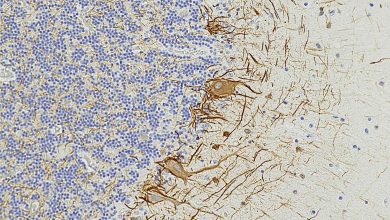

Como a esclerose múltipla prejudica o cérebro muito antes do aparecimento dos sintomas

No cérebro humano, a cadeia leve do neurofilamento (NfL, mostrada em marrom) é vista nas células cerebrais e nos fios…